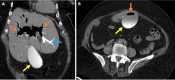

Endoscopic retrograde cholangiopancreatography (ERCP) is a cornerstone procedure for the diagnosis and management of pancreatic and hepatobiliary diseases. Although its diagnostic role has been increasingly supplanted by noninvasive imaging modalities such as magnetic resonance imaging (MRI) and magnetic resonance cholangiopancreatography, the therapeutic applications of ERCP have continued to expand. ERCP is widely used and has a generally favorable safety profile. However, it is important to recognize expected post-procedural imaging findings and serious complications that can arise. The increasing complexity of therapeutic interventions and the growing volume of procedures have led to a higher incidence of complications that often present with overlapping clinical and laboratory features, underscoring the critical role of imaging in differential diagnosis. This review focused on the typical normal ERCP findings and the imaging characteristics of common complications, including pancreatitis, bleeding, ERCP-related infections, perforations, and stent-related complications. Computed tomography (CT) is particularly valuable in timely recognition, management, and surgical decision-making for these complications. Furthermore, MRI offers a radiation-free alternative for managing complications in selected patients. Therefore, radiological modalities, particularly CT and MRI, are critical tools for the rapid diagnosis, management, and surgical decision-making processes for post-ERCP complications.